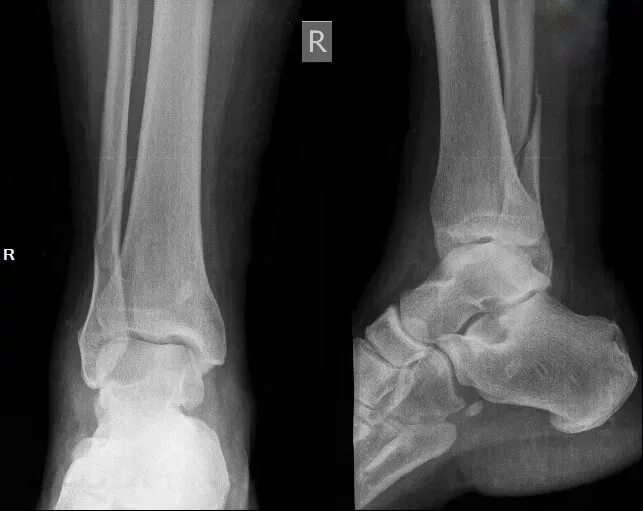

Почему не срастается